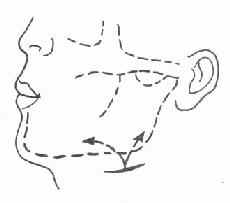

切开引流要点:在下颌骨下缘约2cm处,作与下颌下缘平行切口切开皮肤、皮下组织及颈阔肌后,以血管钳分离引流。注意防止损伤面神经下颌缘支(图3-21)。

图3-21 颌下蜂窝织炎切开引流